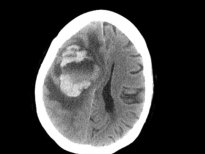

ABD'nin Washington eyaletinin Seattle kentinde yaşayan 69 yaşındaki bir kadın, su yoluyla vücuduna giren amiplerin beynini yemesi üzerine yaşamını yitirdi. Doktorlar, kadının hastalığı yüzünden sinüslerini temiz suyla yıkaması gerekirken musluk suyu kullandığı, amiplerin de musluk suyundan önce burnuna ardından kan yoluyla beynine sızdığı sonucuna vardı.

ABD'de yaşayan bir kadın, su yoluyla burnundan giren amiplerin beynini yemesi nedeniyle hayatını kaybetti.